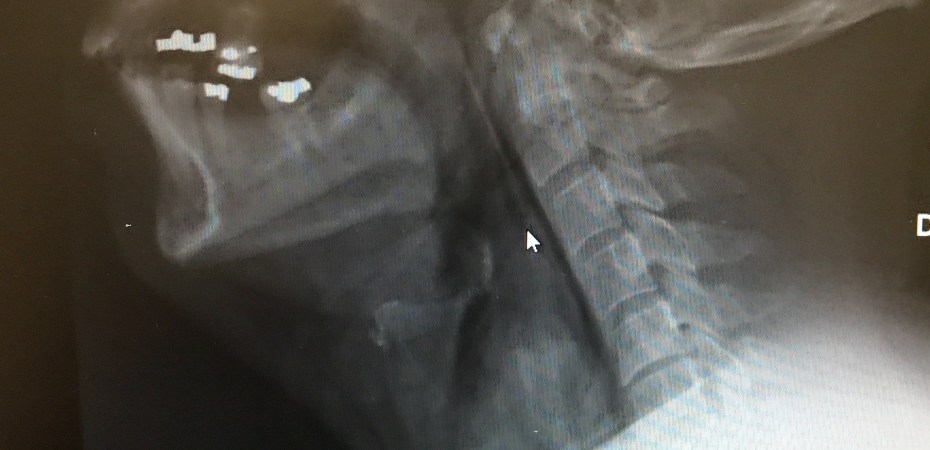

Aujourd’hui, on met le duct-tape de côté et on le remplace par du Pip-Tazo et du Pantoloc intraveineux, car on parle de perforation oesophagienne.